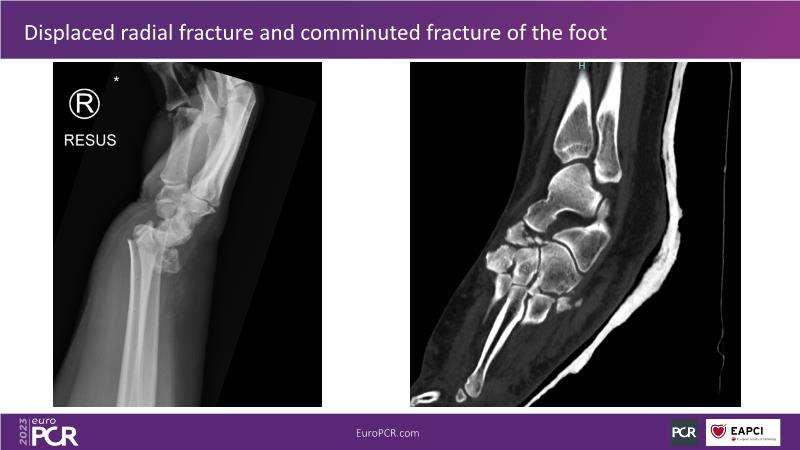

Primary percutaneous pulmonary intervention (pPPI) of acute pulmonary embolism with computer-aided mechanical aspiration

- To share practical experiences from real case scenarios